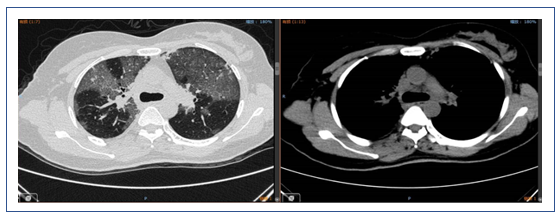

2019年1月16日复查胸部CT:双侧中下肺实变影较1月9日增多(图7)。

图7 患者复查胸部CT与前对比

左:2019年1月16日CT;右:2019年1月9日CT

患者1月4-6日使用激素,然后停用,胸部CT显示部分病变加重,部分病变被吸收;另外,中下肺背部实变比较明显,而且气管和支气管征比较突出,另外,病变沿着气管、支气管束的分布,符合机化性肺炎表现。但是机化性肺炎不能引起类似呼吸衰竭如此严重的情况,所以个人考虑是否为纤维素性机化性肺炎(AFOP),当然需要病理诊断来进一步明确。患者淋巴细胞非常低,这是目前很难解释的,所以还是期待进一步的检查。

该患者的实变处于整个重力依赖区,从双上肺的后段到下面的背段。一方面可能是停用激素后的反弹,另外一方面考虑跨肺压过小,与长期仰卧位机械通气有关,另外,PEEP过高对患者也有不良影响。此类患者如果不用激素,可以考虑俯卧位通气,能够短期迅速缓解患者重力依赖区的实变。我们还是期待后续的检查结果。